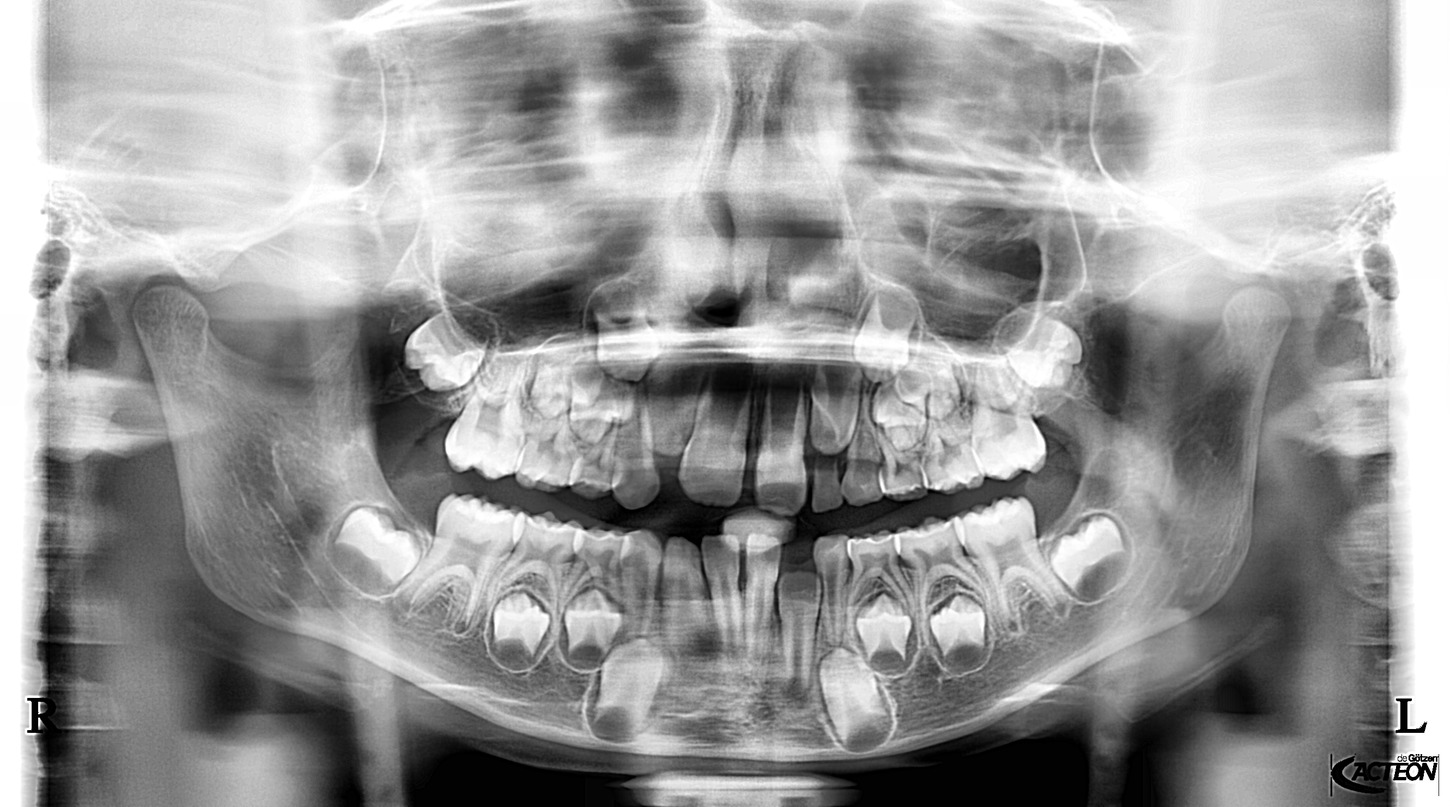

Přesné snímky pro zlepšení diagnostiky. To přináší panoramatické RTG od dodavatele Acteon Satelec, které jsou svými parametry a cenovou dostupností nejlepší volbou pro stomatologické praxe. Volit můžete z mnoha variant (kotvení, rozšiřitelnost o 3D, rozšiřitelnost o kefalometrické rameno atd.) a tím jsou snadno přizpůsobitelné do každého prostoru a každé stomatologické praxe. Jedná se o OPG, která svou kvalitou a ovládáním předčí všechna očekávání a řadí se tak mezi nejpoužívanější OPG na světovém i českém trhu. Poskytuje veškeré panoramatické možnosti pro všeobecnou stomatologii: dentální panoramatickou, klouby i sinusy. Jednoduché nastavení, pohodlí pacienta a rychlé vyšetření. Společnost Fénix Dental dodává všechny přístroje s odborným zaškolením, a to dle individuální potřeby každého uživatele. Díky Aies SW je zobrazení OPG snímků bezkonkurenční. Díky panoramatickému RTG od výrobce Acteon, získáte nejpřesnější diagnostickou hodnotu, která snese i ta nejpřísnější měřítka. Společnost Fénix Dental je přímý zástupce a autorizovaný servis pro produkty Acteon. Prohlédněte si naši nabídku právě zde a neváhejte nás kontaktovat pro bližší informace.